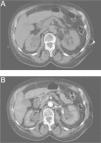

Mujer con hipotensión y fallo renal agudo

J. Martín Cuartero, E. Angulo Hervias, E. Abril Avellanas, R. Larrosa López

Hospital Universitario Miguel Servet. Zaragoza. España